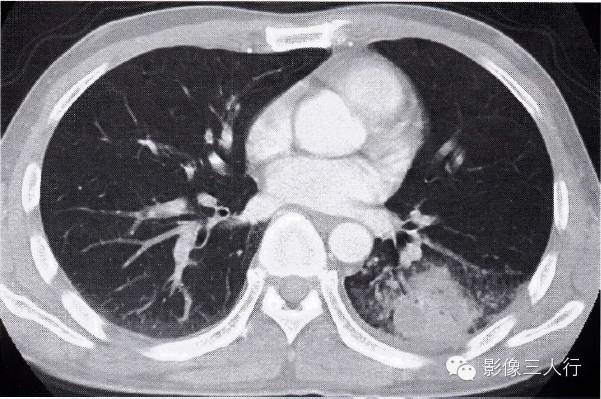

肺结核合并肺癌的CT表现及鉴别诊断

图2-93肺癌在肺结核病灶内

患者痰查结核杆菌阳性,左肺下叶斑片状影,密度较淡,边缘模糊,其内有包块影,大于3cm,有分叶,与胸膜紧贴,肺穿刺为肺鳞癌